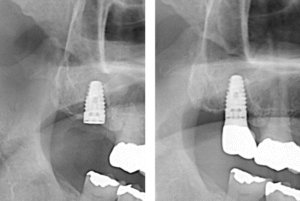

インプラント

インプラント治療

この症例を見る